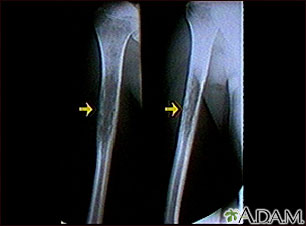

Rayos X de un sarcoma de Ewing

Esta radiografía muestra un tumor óseo maligno (sarcoma de Ewing) del hueso del brazo (húmero). Este tipo de tumor generalmente aparece durante la niñez o la adolescencia.